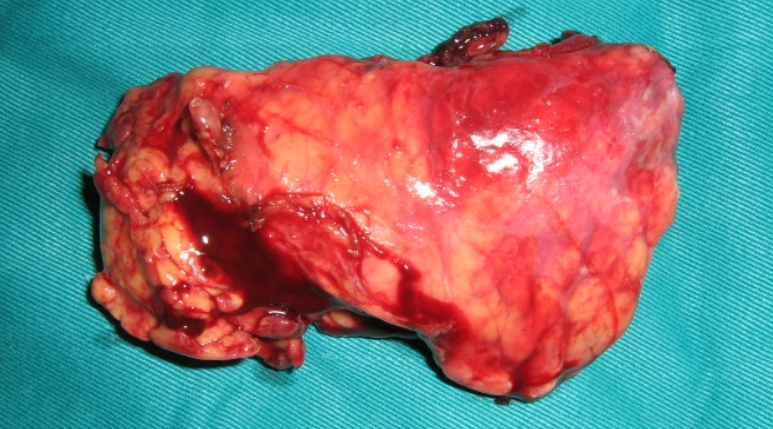

Phẫu thuật cắt thân đuôi tụy ± lách

Phân loại AAST – IV (Lucas III)

-  Tụy:- Cắt bỏ đuôi hoặc thân đuôi tụy

- Cắt thân đuôi tụy (±cắt lách)